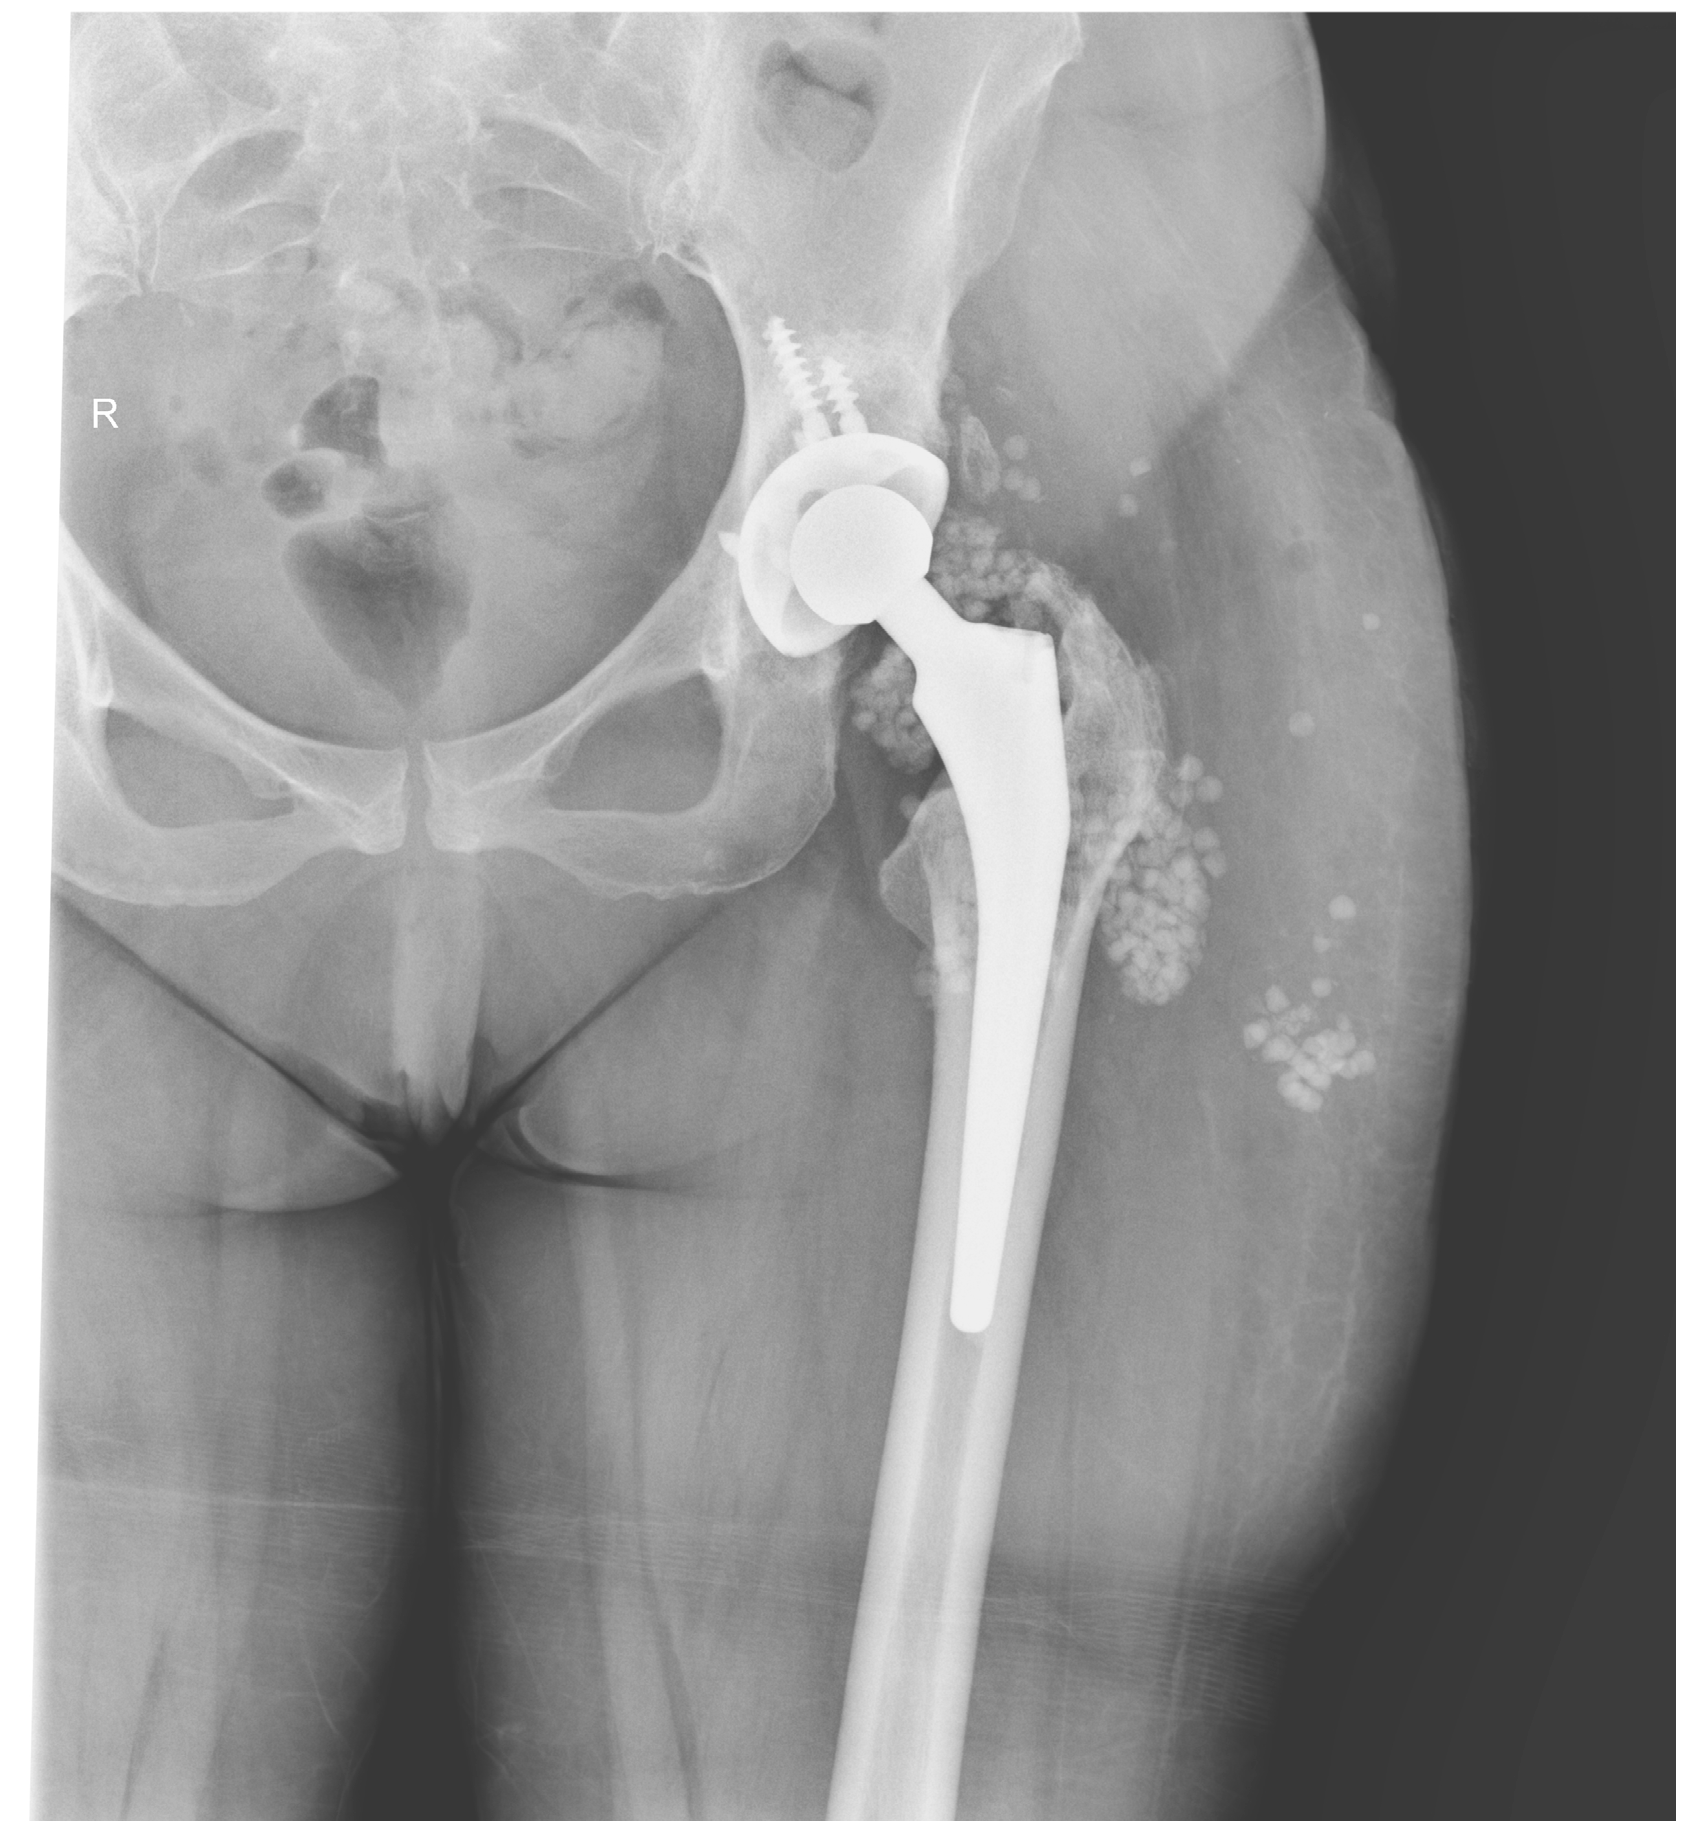

The Efficacy of Antibiotic-Loaded Calcium Sulfate Beads (Stimulan) in Patients with Hip Arthroplasty Infections

2.4. Surgical Procedure